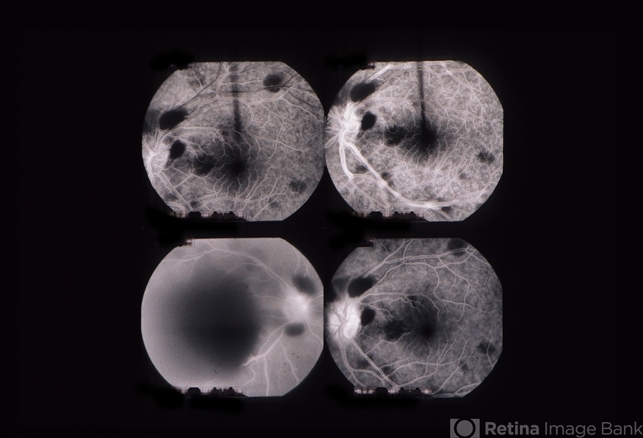

- 39 year female with a long history of chronic back pain treated by a sequence of epidural injections. Following her last injection, she complained of a moderately severe protracted headache and had several attempts at placement of an epidural blood patch without success. Under general anesthesia, she underwent injection of a larger volume of saline in an attempt to stem a presumed CSF leak producing "spinal headache". In the left eye she demonstrated multiple superficial and deep intraretinal hemorrhages associated with mild disc swelling and a central scotoma. In the right eye she showed a posterior subhyaloid and sub-internal limiting membrane hemorrhage with buffy coat layering superiorly. The visual acuity measured hand motions OD, 20/200 OS. The patient underwent a surgical evacuation of the sub-ILM hemorrhage.